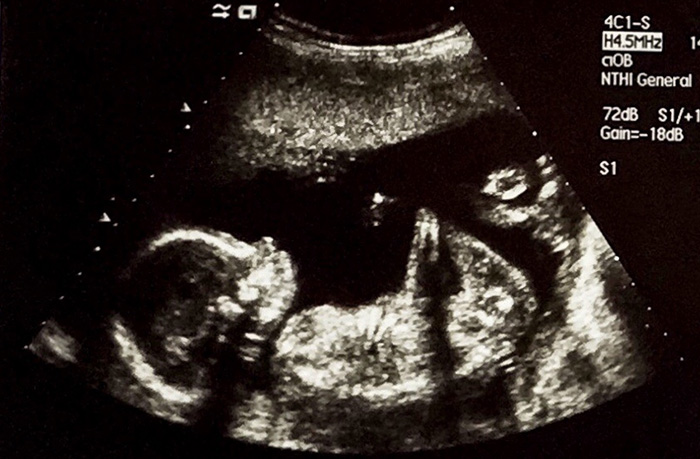

ECHOGRAPHIES DE GROSSESSE

Cet examen est proposé pour une bonne prise en charge de la grossesse en précisant la position et le nombre de fœtus, l’état de la croissance, la morphologie fœtale et la qualité des échanges entre la mère et le fœtus.

Selon la situation, un avis peut être nécessaire auprès du praticien qui suit la future maman ou auprès d’un centre de diagnostic anténatal. En France, trois examens sont proposés aux environs de 12 SA, 22 SA et 32 SA (SA pour Semaines d’Aménorrhée c’est-à-dire depuis le 1er jour des règles. Connaître l’âge de la grossesse est primordial pour détecter une anomalie de la croissance). Au cours de l’échographie du 1er trimestre, certaines mesures couplées à une prise de sang chez la future maman, peuvent permettre de participer au dépistage de la trisomie 21 (cf Echographie du 1er trimestre).

Par voie abdominale le plus souvent, la voie endovaginale peut être nécessaire pour compléter l’examen. Visualisation systématique de critères anatomiques précis (référencés par le collège français d’échographie fœtale CFEF) concernant le fœtus et les annexes.